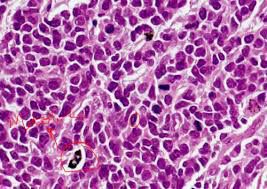

Enterochromaffin (EC) cells (also known as Kulchitsky cells) are a type of enteroendocrine cell, and neuroendocrine cell. They reside alongside the epithelium lining the lumen of the digestive tract and play a crucial role in gastrointestinal regulation, particularly intestinal motility and secretion.They were discovered by Nikolai Kulchitsky